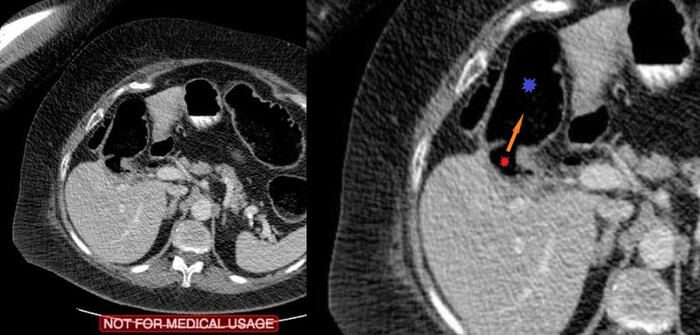

Тут позволю возразить: представленное выше - одно из встречающихся тяжёлых последствий черепно-мозговой травма, а именно т.н. ДАП или диффузное аксональное повреждение:

Диффузное аксональное повреждение (ДАП) - это тяжелая форма травматического повреждения головного мозга возникающая за счет воздействия сдвигающих сил. Диффузное аксональное повреждение потенциально трудно диагностировать, поскольку проявления при компьютерной томографии могут быть едва различимы, однако оно может приводить к тяжелым неврологическим нарушениям.

Диффузное аксональное повреждение является результатом воздействия сдвигающих сил возникающих при ротационном ускорении (реже торможении). Из-за разной плотности (относительная масса в единице объема) белого и серого вещества сдвиг происходит преимущественно в аксонах на границе серого и белого вещества, это и отражает название патологии. В большинстве случаев эти силы приводят и к повреждению клеток, что проявляется отеком. Но полный разрыв аксонов происходит только в тяжелых случаях.